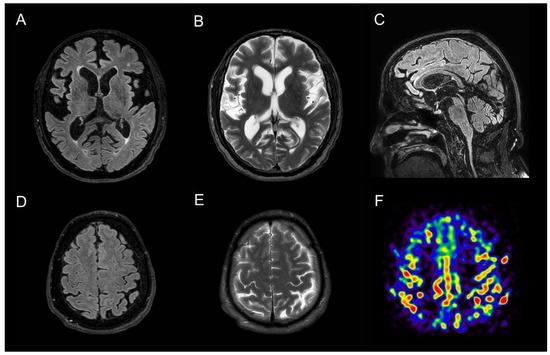

A 63-year-old man, with no previous history of neurological disorder, presented with a one-year history of slowness of movement as well as gait difficulties with postural instability and complained of episodes of falls and swallowing problems. He also reported a five-year history of vivid dreams with dream-enacting behaviour, suggestive of REM sleep behaviour disorder (RBD), and a two-year history of erectile dysfunction. Six months before the visit, he developed laryngeal stridor during sleep and severe nocturnal dyspnea attacks resulting in acute respiratory failure requiring intubation and subsequent tracheostomy. His family history was negative for neurodegenerative disorders. A neurologic examination showed horizontal gaze-evoked nystagmus, bradykinesia, rigidity, and mild rest and postural tremor that was more evident on the left side. He had reduced right arm swing when walking and a shuffling gait. Neuroimaging studies were carried out to differentiate atypical parkinsonian syndromes and to rule out alternative diagnoses. A structural brain 3T MRI showed temporal atrophy with relative preservation of other cortical areas and demonstrated high-convexity tight sulci (Figure 1). Subcortically, midbrain atrophy was evident (the “hummingbird” sign). An arterial spin labelling (ASL)-MRI documented relative hyperperfusion of the high-convexity area with relative preservation of other brain regions. Brain perfusion SPECT imaging confirmed relative hyperperfusion in the high-convexity area. [123I] FP-CIT SPECT demonstrated a bilateral dopaminergic nigrostriatal denervation more prominent in the right putamen. The magnetic resonance parkinsonism index (MRPI 2.0) [1], a reliable imaging morphometric marker for the diagnosis of progressive supranuclear palsy (PSP), was manually calculated and was suggestive of PSP. A routine CSF analysis was unremarkable, and CSF amyloid beta (Aβ42) and tau (total and phosphorylated tau) levels were normal. Although the clinical and radiological presentation was suggestive of PSP, some elements were atypical. First, vertical supranuclear palsy or slow velocity of the vertical saccades, which are clinical features with high diagnostic relevance for PSP, were absent in this patient. Second, laryngeal stridor is rare in PSP and is typically present in other atypical parkinsonisms, such as multiple system atrophy. Recently, a new disorder characterized by nonREM and REM parasomnias, stridor, and gait instability resembling PSP (PSP-like syndrome) has been described, which occurs in association with antibodies against extracellular epitopes of IgLON5, a neuronal cell adhesion protein. Autoantibodies for IgLON5 IgG were tested in both the serum and CSF using a commercially available cell-based assay and returned positive in our patient (Supplementary Figure S1).

Anti-IgLON5 disease is a very rare clinical entity characterized by distinctive sleep disorders associated with a broad variety of neurological symptoms, such as parkinsonism with gait instability, bulbar symptoms, and dysautonomia. This condition has been first described in 2014 [2], and since then, more than 60 cases of anti-IgLON5 disease have been reported in the literature [3]. Its pathophysiology still remains unknown, but it seems to be the result of a combination of both autoimmune and neurodegenerative processes. Characteristic neuropathologic findings include a lack of inflammatory infiltrates, neuronal loss, gliosis, and neuronal accumulation of hyperphosphorylated tau protein (both 3-repeat and 4-repeat isoforms) found predominantly in the hypothalamus and the tegmental brainstem nuclei [2]. MRI findings are normal or nonspecific in 81.8% of cases [3,4,5]. The most frequent abnormality is brainstem atrophy [6]. Ioflupane SPECT abnormalities, though scarcely described, have been reported in anti-IgLON5 disease, probably reflecting nigrostriatal dopaminergic degeneration in the context of the tauopathy component of the disease [7]. In this case, midbrain atrophy documented by a structural MRI and dopaminergic denervation shown by a dopaminergic SPECT oriented initially for a diagnosis of PSP. Furthermore, the imaging morphometric marker MRPI was also indicative of PSP. Interestingly, the MRI also demonstrated “high-convexity tight sulci”, an established neuroimaging biomarker of CSF dynamics disorders and defined as compression of sulci at the vertex, enlarged CSF spaces in the Sylvian fissure, and ventriculomegaly. Although “high-convexity tight sulci” was originally identified in individuals with symptomatic normal-pressure hydrocephalus (NPH), it has been also found in other conditions [8]. Similarly, hyperperfusion of the high-convexity area on perfusion imaging has been previously linked to NPH [9]. We believe that relative convexity hyperperfusion in our case is apparent and may reflect the increased gray matter density of the convexity, as it has been demonstrated in NPH [9]. Although CSF dynamics abnormalities have been observed in other conditions [8], to the best of our knowledge, this is the first time that neuroimaging reveals CSF dynamics problems in anti-IgLON5 disease. This case highlights the fact that anti-IgLON5 disease can exhibit the clinical and radiological changes seen in PSP patients and that neuroimaging markers of CSF dynamics problems (“high-convexity tight sulci” on an MRI and hyperperfusion of the high-convexity on both an ASL-MRI and a perfusion SPECT) may be found in IgLON5. Further case descriptions and case−control neuroimaging studies are warranted to characterize neuroimaging abnormalities in this condition. Neuroimaging studies are also required because CSF dynamics abnormalities are detectable in vivo only, and neuropathological studies cannot be used to investigate this phenomenon. Although clinical presentation may be very distinctive, imaging biomarkers may potentially assist the diagnosis of this rare condition. The early recognition of anti-IgLON5 diseases is essential as immunotherapy seems to be crucial for clinical outcomes.

Figure 1. MRI findings in a case of anti-IgLON5 disease: (A,B) axial T1-weighted and T2-weighted sequences demonstrate marked temporal atrophy with relative preservation of other cortical regions; (C) sagittal T1-weighted brain MRI sequences show midbrain atrophy (the “hummingbird sign”); (D,E) axial T1-weighted and F T2-weighted sequences showed “high-convexity tight sulci”; “high-convexity tight sulci” is defined as the compression of sulci at the vertex, enlarged CSF spaces in the Sylvian fissure, and ventriculomegaly; (F) arterial spin labelling (ASL)-MRI documented hyperperfusion in the high-convexity area with relative preservation of other brain regions.